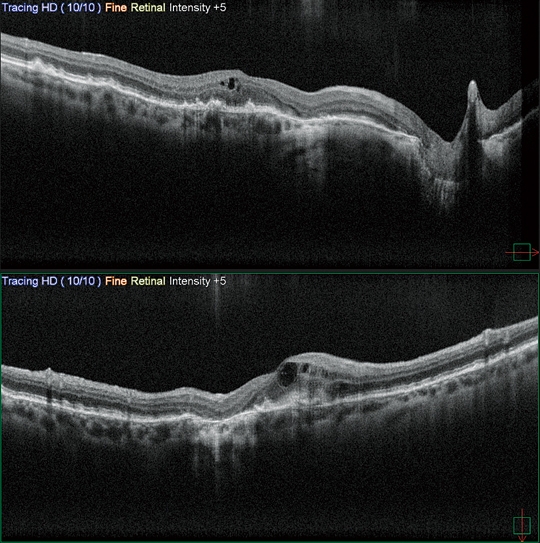

高清廣域OCT*

Mirante的掃描區域可達16.5 x 12毫米,單次拍攝就可實現包括黃斑和視盤的廣域診斷。超精細模式和高清自動追蹤功能可提供從玻璃體到脈絡膜的高質量圖像來觀察細微的病理改變。

* 適用于SLO/OCT型。

Fly同步瀏覽功能

Fly同步瀏覽功能可滾動查看同一區域不同模式的影像,極大地提高了多模態成像的實用性。